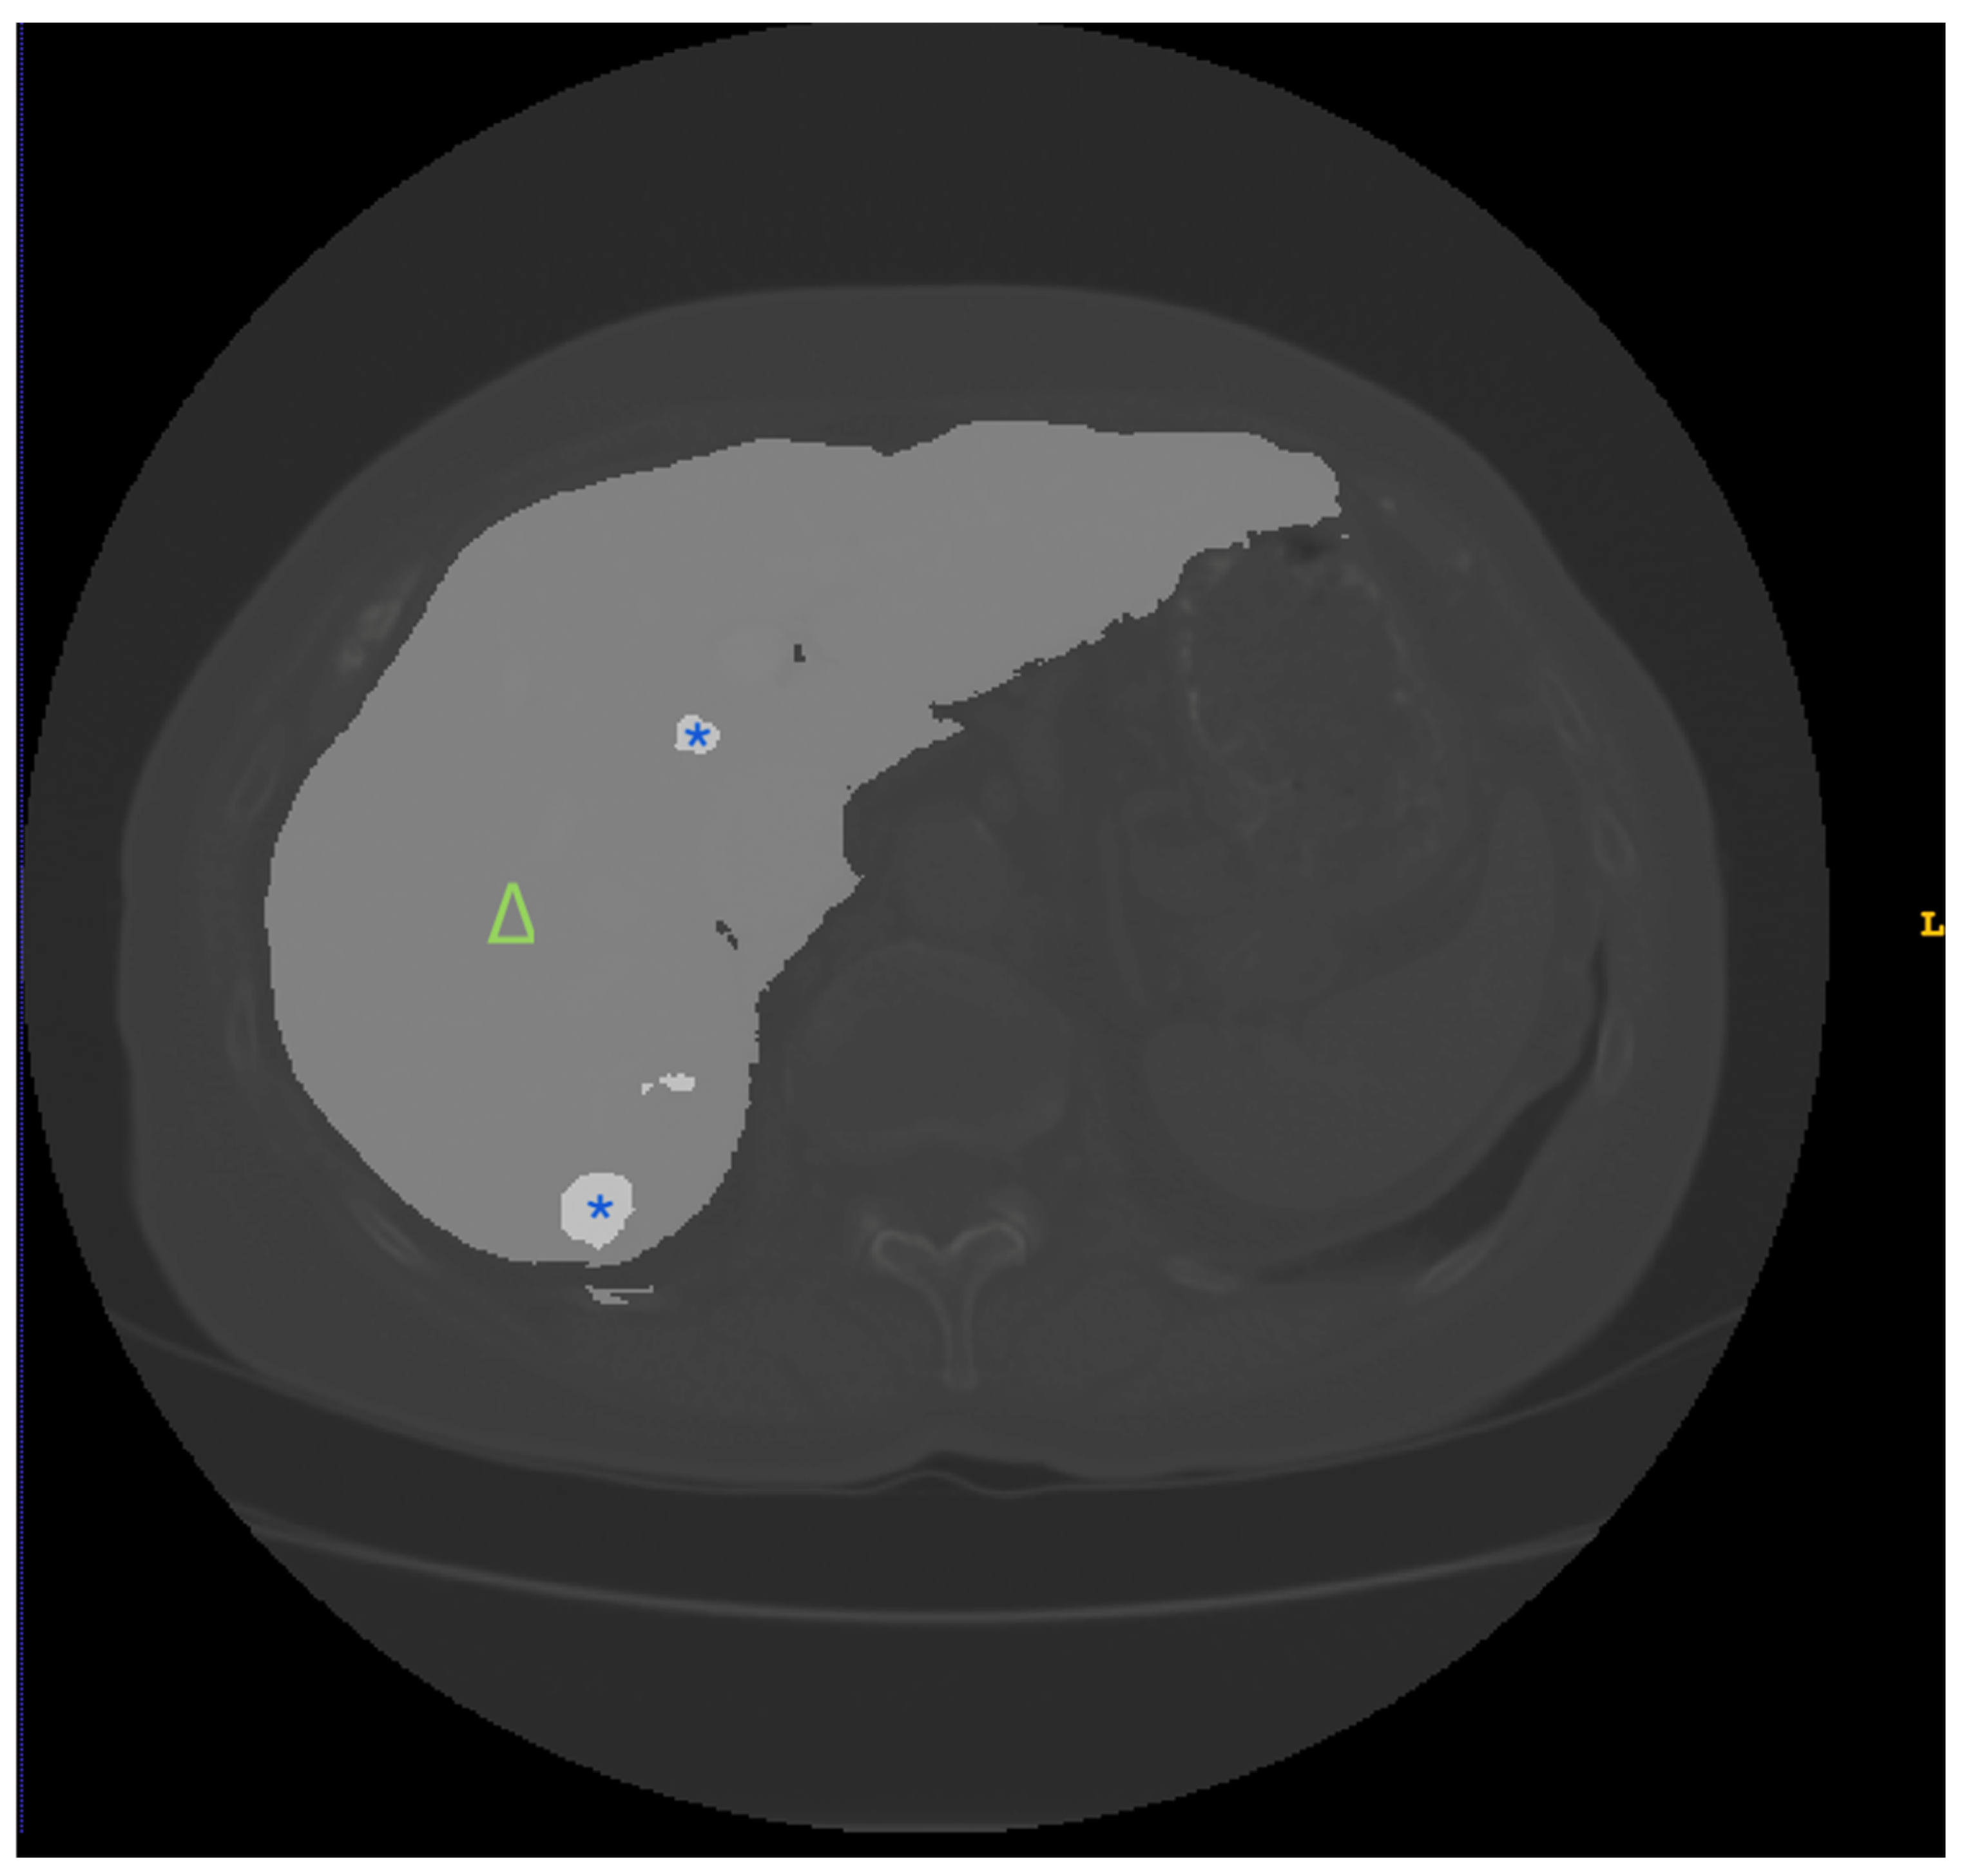

| 3DIRCADb | CT scans from 20 patients with annotations for liver and liver tumor segmentation | Detailed 3D reconstruction data aid the development of segmentation algorithms for complex liver structures | Small sample with limited case types |